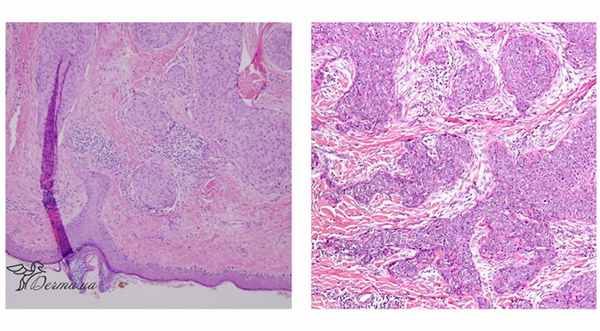

Гистологическое строение эккринной поромы. Внутриэпидермальная злокачественная порома in situ состоит из гнезд маленьких базалоидных клеток с примесью более крупных атипичных клеток с полиморфными ядрами и атипичными митозами, расположенных в толще эпидермиса. Возможна также диффузная инфильтрирация эпидермиса единичными атипичными клетками, имитирующая экстрамаммарную болезнь Педжета.

Инфильтрирующая форма злокачественной эккринной поромы состоит из внутридермальных комплексов мелких базалоидных клеток, вероятно, оставшихся от поромы, соседствующих с комплексами более крупных атипичных клеток. Абортивные протоки потовых эккринных желез в виде маленьких расщелин располагаются в пределах дермаль-ных узелков, наряду с хорошо развитыми ту-булярными структурами.

Для злокачественной эккринной поромы характерна акантотическая трабекулярная эпидермальная пролиферация, с наличием гнезд светлых опухолевых клеток. Опухолевые клетки обычно полигональные, с эозинофильной цитоплазмой и круглыми или овальными ядрами, содержащими мелкие нук-леолы. Часто выявляются фокусы плоскоклеточной метаплазии с формированием «роговых жемчужин», микронекрозы, дистрофическая кальцификация. Митозы и анапластичес-кие клетки редки.

Результаты: При микроскопии отмечается удлиненный эпидермис, состоящий из связанных кластеров атипичных эпителиальных опухолевых пороидных клеток, солидных агрегатов опухолевых клеток и дуктальных структур, а также кистозных агрегатов из эпителиальных клеток. Заметные митотические фигуры и часто наблюдаются атипичные митозы.

Макроскопически порокарцинома представляет собой экзофитно растущий узел на широком основании. При микроскопии новообразования в толще эпидермиса выявляются гнезда мелких базалоидных клеток с включениями более крупных клеток с признаками атипии или чередующиеся гнезда базалоидных клеток и структуры, состоящие из атипичных клеток. Атипичные клетки порокарциномы имеют полиморфные гиперхромные ядра. Иногда одиночные крупные клетки диффузно располагаются в неизмененном эпидермисе, из-за чего гистологическая картина порокарциномы может напоминать болезнь Педжета.

В скоплениях атипичных клеток могут просматриваться протокообразные структуры, участки некроза, небольшие полости и «роговые жемчужины». Вокруг клеточных скоплений видны признаки инфильтрации. При длительном существовании порокарциномы атипичные клетки могут проникать в дерму, близлежащие волосяные фолликулы, периневральные пространства, стенки кровеносных и лимфатических сосудов. При проведении иммуногистохимического исследования определяется положительная реакция с альфа-лактатальбуминовым антигеном, антигеном эпителиальных мембран и карциноэмбриональным антигеном.